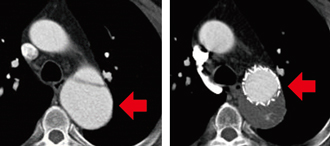

胸部大動脈瘤に対する開窓型ステントグラフト